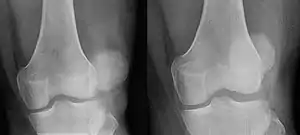

| Patellar luxation on radiograph: Left before, right after reduction; after reduction, the patella is still displaced. | |